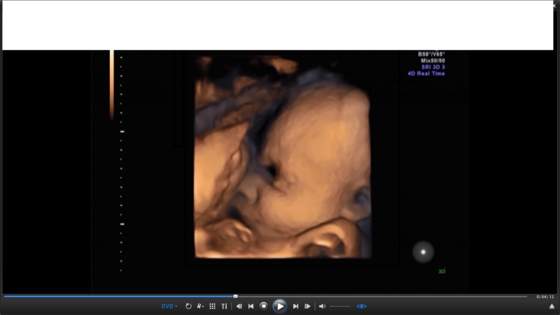

Starasz się o maleństwo, wiesz, że zostaniecie rodzicami a może masz już dziecko? Poszukujesz informacji, chcesz się podzielić swoim doświadczeniem? Dołącz do naszej społeczności. Rejestracja jest bezpieczna, darmowa i szybka. A wsparcie i wdzięczność, które otrzymasz - nieocenione. Podoba Ci się? Wskakuj na pokład! Zamiast być gościem korzystaj z wszystkich możliwości. A jeśli masz pytania - pisz śmiało.